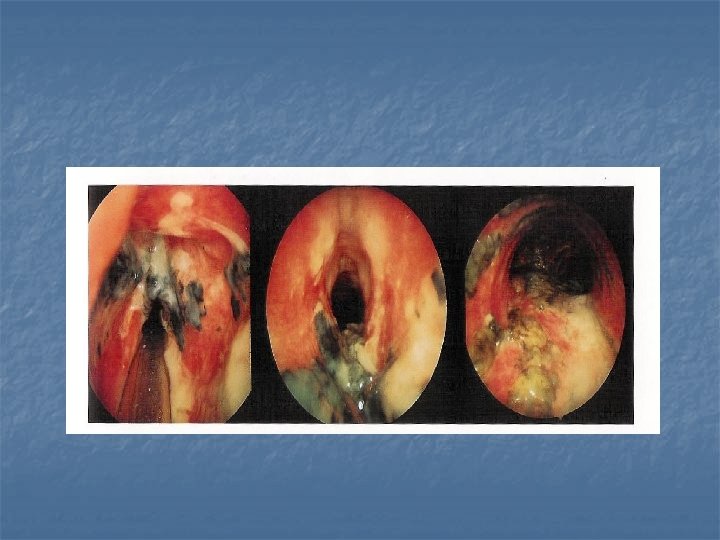

n Recurrent respiratory papillomatosis: n n 2/3 before age 15 rarely malignant change HPV 6 -11 Risks: n n n younger first time mother (condyloma acuminata) Lesions: wart like (cluster of grapes ) Types : n n n SSX: n n juvenile Senile Hoarseness stridor RX; n n laser excision , microdebrider Adjunctive therapy: acyclovir , interferon …